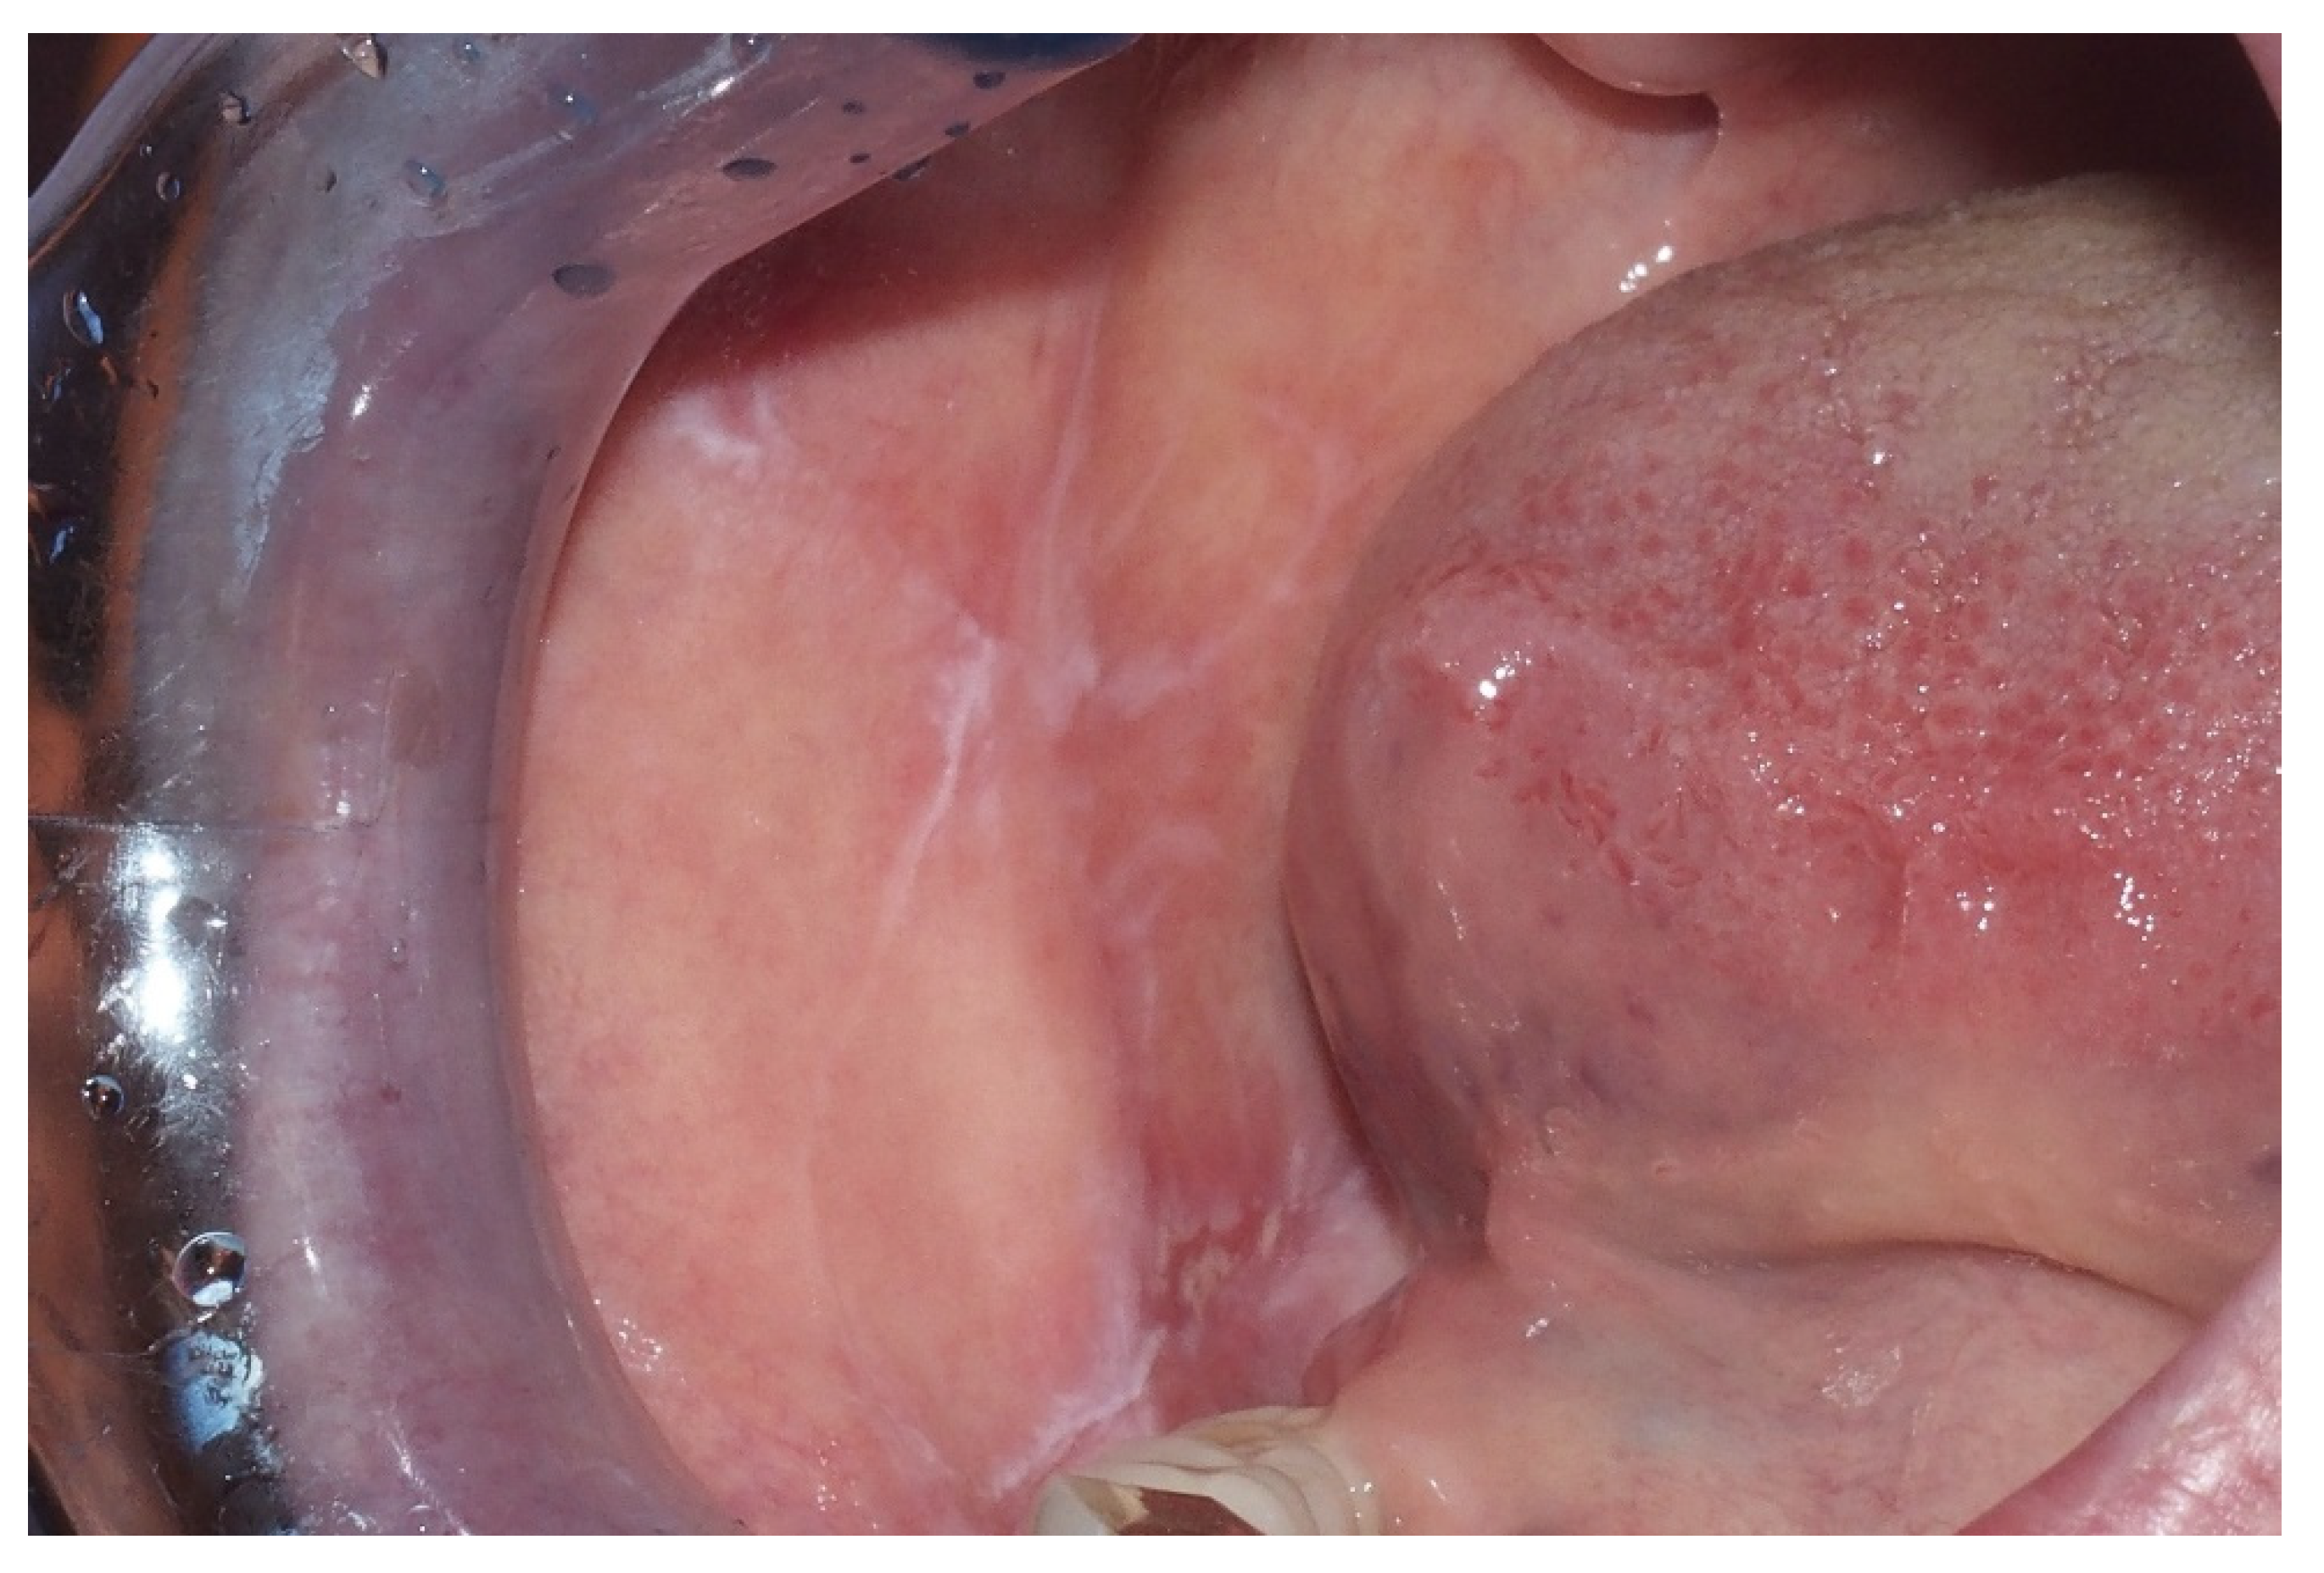

2.1. Leukoplakia

2.2. Erythroplakia